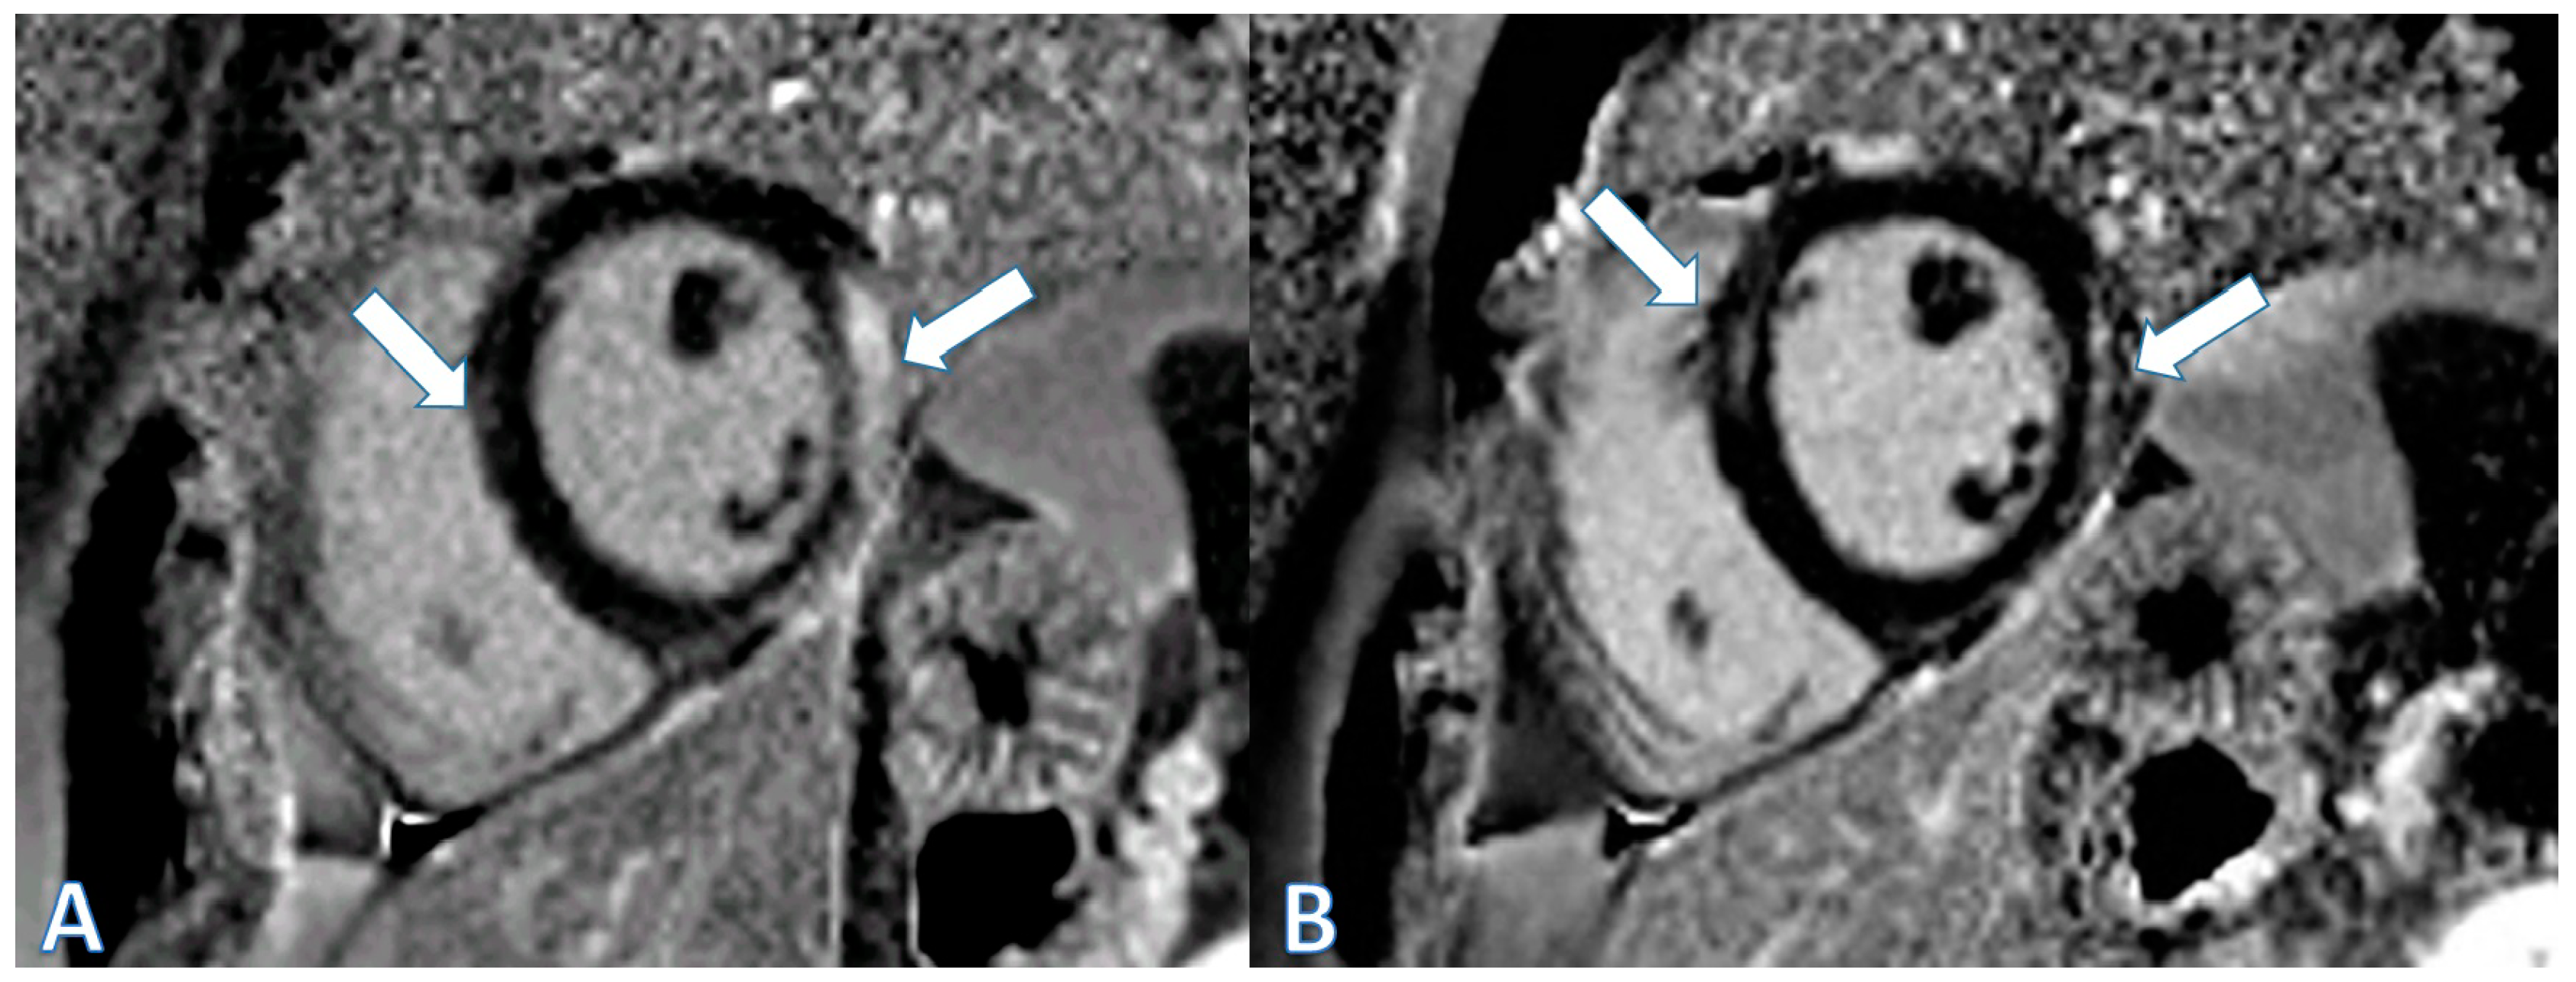

| CMR at hospitalization | LGE of both pericardial leaves and foci of late subepicardial enhancement on the basal inferolateral, lateral, and inferior walls | LGE at the level of the pericardial leaves and a basal inferolateral subepicardial focus | Edema and LGE in the lower-middle, inferolateral, and anterolateral segments | Edema and LGE at the anterolateral, basal-mid inferolateral and basal inferior segments, and intramyocardial in the mid-inferoseptal and apex segments |

| Control CMR at 6–9 months | Persistence of LGE on the inferolateral wall | - | LGE in the inferolateral and anterolateral walls | LGE intramyocardial and subepicardial at inferolateral, anterolateral, and inferoseptal walls (reduced extent) |